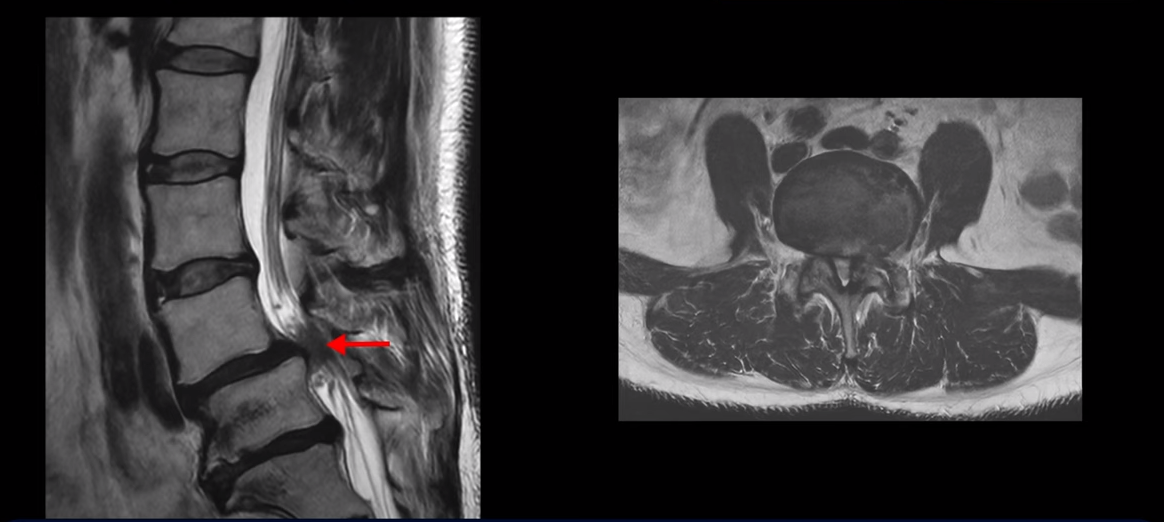

제가 먼저 이 환자분 MRI를 보면서 설명 드린 후 이분 말씀 더 들어보겠습니다. 보시다시피 두 마디가 심하게 퇴행되어 있고

4번 5번에는 척추뼈가 밀려나간 전방전위증이 있습니다.

4번 5번에 심한 중심성 협착도 있습니다.

양쪽 신경 가지가 빠져 나가는 추간공도 왼쪽 오른쪽 모두 좁아져 있습니다.

5번 1번에는 가운데로는 디스크가 밀려나와 있습니다.

이건 아주 오래된 퇴행성디스크로 보입니다. 그래서 이 환자분은 양쪽 엉덩이와 다리가 모두 저리고 아픈 게 양쪽 추간공 문제 때문일 수도 있고 중심성 협착 때문일 수도 있습니다. 퇴행성디스크 때문에 아플 가능성은 상대적으로 적어보입니다.